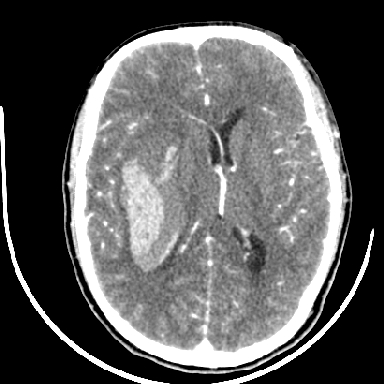

标题: CT6056:脑出血(血管畸形?) [打印本页]

标题: CT6056:脑出血(血管畸形?)

m 40突发头痛左侧偏瘫3小时

考虑高血压性脑出血,依据:

1是高血压性脑出血的好发部位,形态呈肾形,是高血压性脑出血的常见形状

2增强时占位效应加重了,考虑出血还没有停止

3病灶周围水肿不是太厉害,一般肿瘤出血水肿多非常明显

4病灶周围的‘软组织’影没有明显的强化

5至于脑血管畸形引起的出血,暂时没有看到明显的畸形血管影,也不太支持

支持右侧基底节脑出血

右侧基底节区脑出血.

支持右侧基底节区(主要为外囊区)原发性脑出血。

另附部分资料:“血液溢出血管外形成血肿,其内含有大量血红蛋白、血浆白蛋白,球蛋白,因这些蛋白对x线的吸收系数高于脑质,故ct呈现高密度阴影,ct值达40~90h,最初高密度灶呈非均匀一致性,中心密度更高,新鲜出血灶边缘不清。基底节区血肿多为“肾”型,内侧凹陷,外侧膨隆,因外侧裂阻力较小,故向外凸,其它部位血肿多呈尖圆形或不规则形”

术中抽出40ml陈旧血液,血肿底部似见一条索血管影